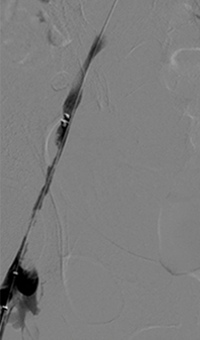

Acute DVT left lower extremity revascularization

47 year old male presented with leg swelling ~2 weeks.

Procedural steps

• Power Pulse delivery of 10mg tPA followed by

• 20 minute dwell time

• Total runtime was 300 seconds

Acute DVT Left Lower Extremity Revascularization pre-treatment angio.

Acute Iliofemoral thrombus pre-treatment

IVC Filter placed (left image)

Acute DVT Left Lower Extremity Revascularization post-treatment.

Post ZelanteDVT  pharmacomechanical thrombectomy

Case images courtesy of David Wilson M.D. – Harbin Clinic, Rome, Georgia – December 19, 2015